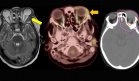

La ecografía renal reveló una obstrucción bilateral de la unión ureteropélvica (UEP) debido a cálculos de 1,4 cm en el lado derecho y 1 cm en el izquierdo, con hidronefrosis moderada derecha y severa izquierda. Estos hallazgos fueron confirmados por urografía retrógrada.

Ante el diagnóstico de obstrucción bilateral aguda, se realizó pielografía retrógrada bilateral, colocación de stents ureterales y cistoscopia. Posteriormente, la presión arterial descendió rápidamente a 140/80 mmHg, con mejoría paralela de la función renal (creatinina de 2,2 mg/dL en descenso hacia el valor basal).